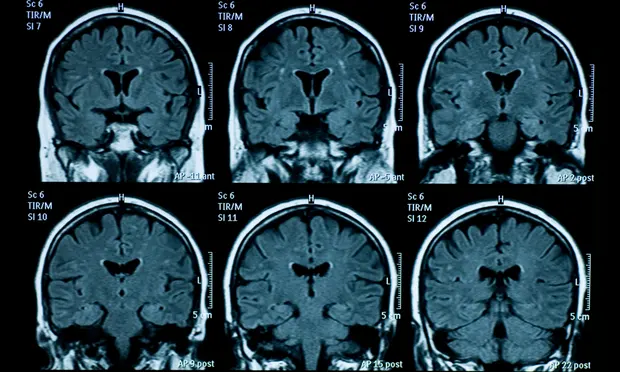

Lần đầu tiên trực tiếp quan sát được ‘yếu tố kích hoạt’ bệnh Parkinson trong mô não người

Lần đầu tiên, các nhà khoa học đã trực tiếp quan sát và định lượng được các cụm protein được cho là nguyên nhân khởi phát bệnh Parkinson. Kết quả này đã đánh dấu một bước tiến lớn trong nghiên cứu căn bệnh thần kinh phát triển nhanh nhất thế giới.

Não của thanh thiếu niên có dấu hiệu lão hóa nhanh hơn sau giãn cách xã hội

Nghiên cứu cũng cho thấy sức khỏe tinh thần của người tham gia cũng kém đi, nhưng các nhà khoa học không chắc rằng liệu điều này có liên quan đến sự khác biệt về tuổi não (brain age) hay không.